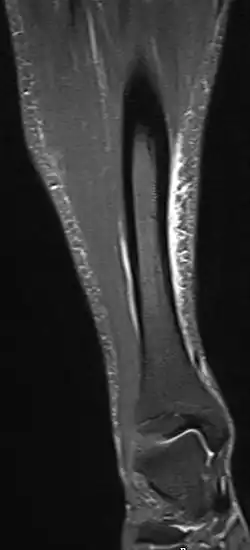

Other potential causes include stress fractures, compartment syndrome, nerve entrapment, and popliteal artery entrapment syndrome.[19] If the cause is unclear, medical imaging such as a bone scan or magnetic resonance imaging (MRI) may be performed.[3] Bone scans and MRI can differentiate between stress fractures and shin splints.[13]